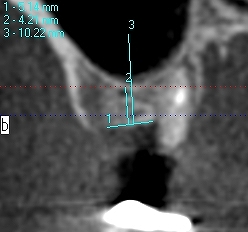

上顎洞までの距離はしっつかりとあるわけでもありません

この骨に上顎洞を持ち上げ5㎜幅10㎜長さのインプラントを埋入

していきました